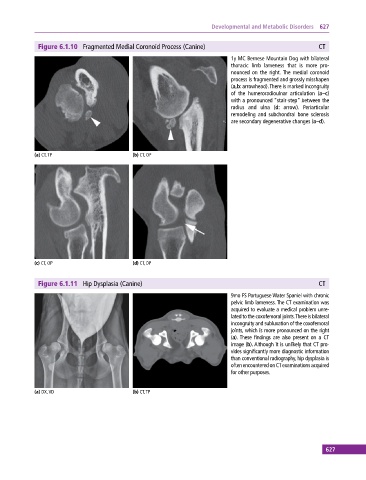

Figure 6.1.10 Fragmented Medial Coronoid Process (Canine) CT

1y MC Bernese Mountain Dog with bilateral

thoracic limb lameness that is more pro

nounced on the right. The medial coronoid

process is fragmented and grossly misshapen

(a,b: arrowhead). There is marked incongruity

of the humeroradioulnar articulation (a–c)

with a pronounced “stair‐step” between the

radius and ulna (d: arrow). Periarticular

remodeling and subchondral bone sclerosis

are secondary degenerative changes (a–d).

(a) CT, TP (b) CT, OP

(c) CT, OP (d) CT, DP

Figure 6.1.11 Hip Dysplasia (Canine) CT

9mo FS Portuguese Water Spaniel with chronic

pelvic limb lameness. The CT examination was

acquired to evaluate a medical problem unre

lated to the coxofemoral joints. There is bilateral

incongruity and subluxation of the coxofemoral

joints, which is more pronounced on the right

(a). These findings are also present on a CT

image (b). Although it is unlikely that CT pro

vides significantly more diagnostic information

than conventional radiography, hip dysplasia is

often encountered on CT examinations acquired

for other purposes.

(a) DX, VD (b) CT, TP